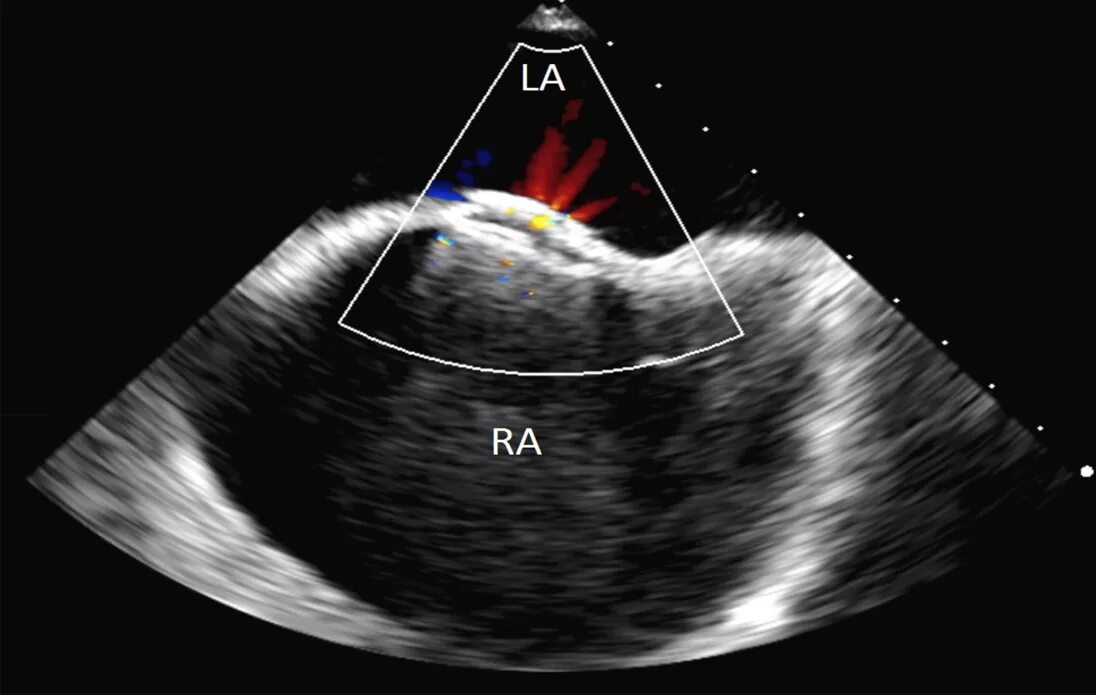

Аневризма мпп без